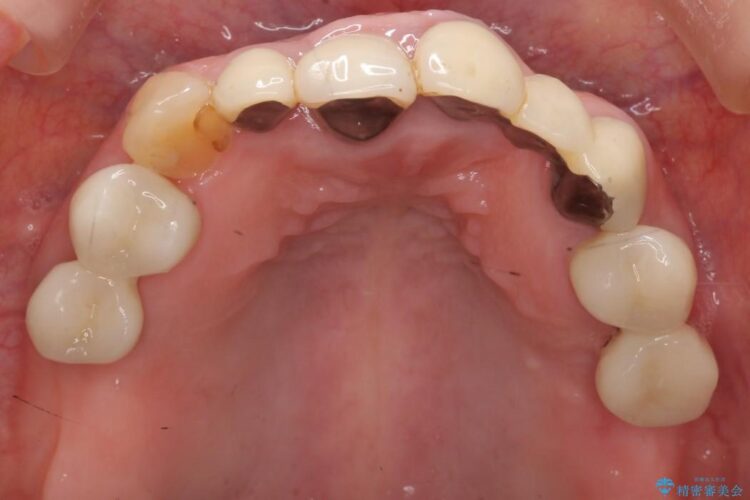

前歯のかぶせ物に関しましては、内面が金属で覆われているため歯茎にその色が透けて見えるという審美的な問題と、かぶせ物と歯の境界が不適合であるという問題がありました。

今回の症例では金属の色が透けていることを気にされていたので、土台から金属を除去し、金属を使用していないオールセラミックのかぶせ物を使用することとしました。